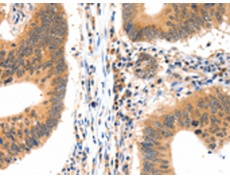

IHC positive control: |

Human colon cancer and Human ovarian cancer |

IHC Recommend dilution: |

15-50 |